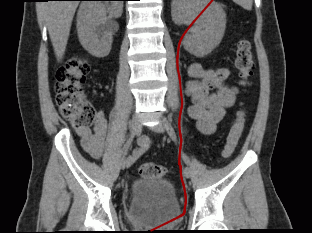

Straightened involute. The mode is set by default. In the straightened involute curve window (Fig. 5.10), the curve built by the user is transformed into a straight line. The distortions of space along the curve are marginal and increase with distance from the curve. We recommend this mode when the region of interest is placed near the curve. This option provides for the highest possible level of detail along the curve.

Involute curve in orthogonal planes (Fig. 5.11). Unlike the Straightened involute mode, this mode provides for a lower distortion degree at a distance from the curve, but the level of detail along the curve is also lower. Unlike the Involute curve from first to last point, this mode is less dependent on the position of points on the curve. It is used when you need an involute similar to an orthogonal projection. The orthogonal projection is chosen automatically to provide for the highest possible level of detail along the curve. Still, the level of detail along the curve is lower compared to other curve modes.

Involute curve from first to last point (Fig. 5.12). Compared to the Straightened involute mode, the distortion degree at a distance from the curve is lower, but the level of detail along the curve is also lower. The involute is highly dependent on the position of the first and the last point on the curve. The level of detail along the curve is greater than in the Involute curve in orthogonal planes mode.